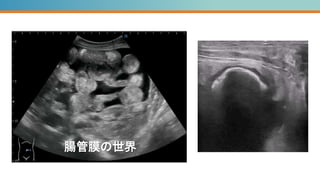

腸管膜の世界

詳しいあて方に関しては↓のURLでチェック

腹部超音波検査 救急外来・病棟で役立つ超音波検査パート1

4:27-10:35 https://www.youtube.com/watch?v=2y4bBZkpzk0